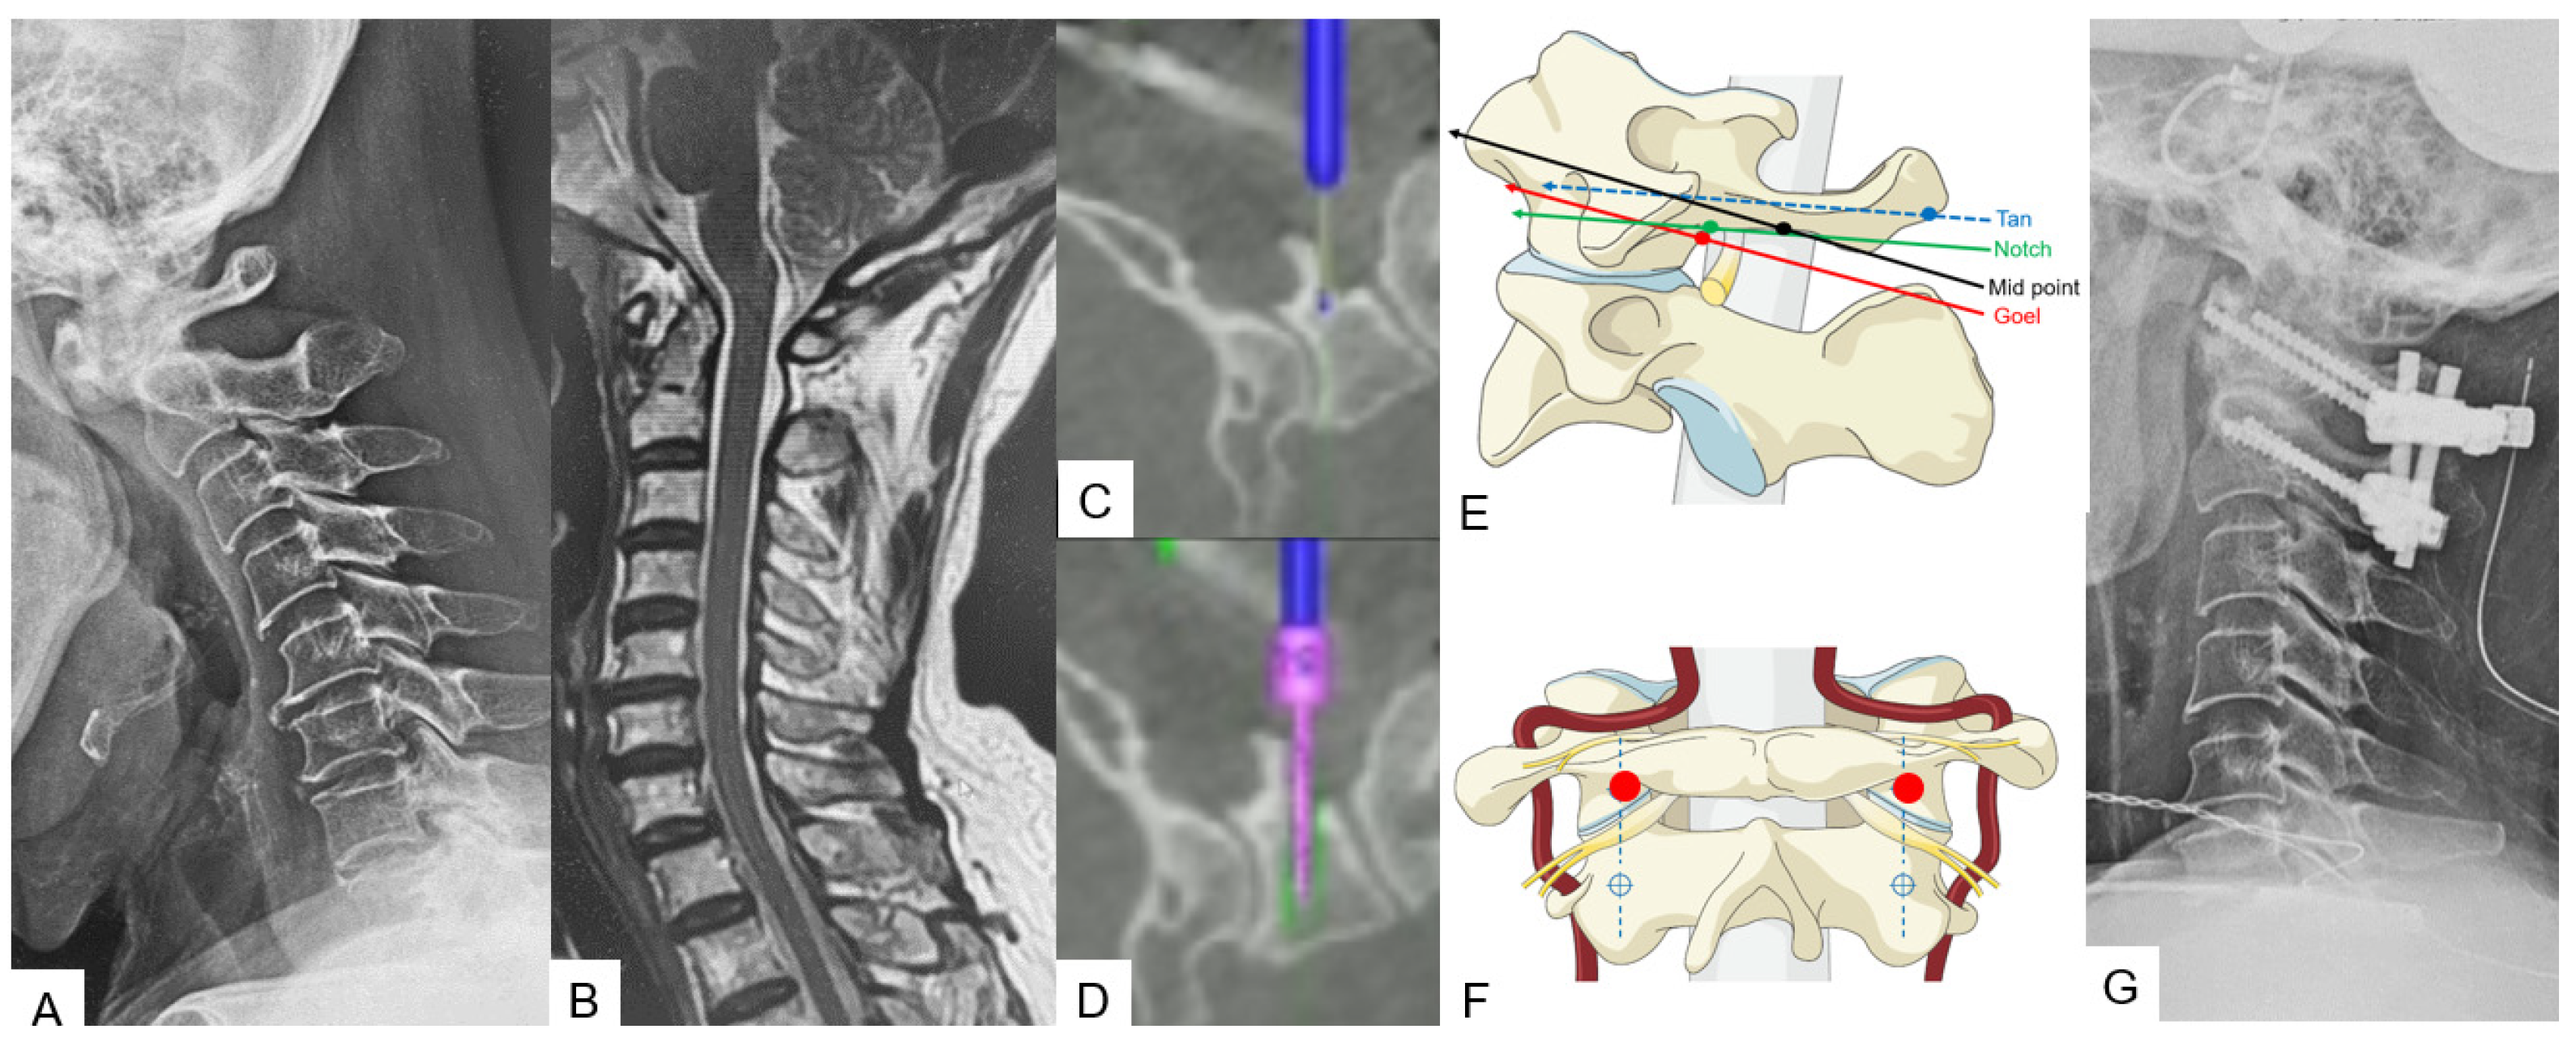

2.2.3. Midpoint Technique for C1 Lateral Mass Screw (LMS) Placement

2.2.4. Minimally Invasive Cervical Pedicle Screw Fixation (MICEPS)